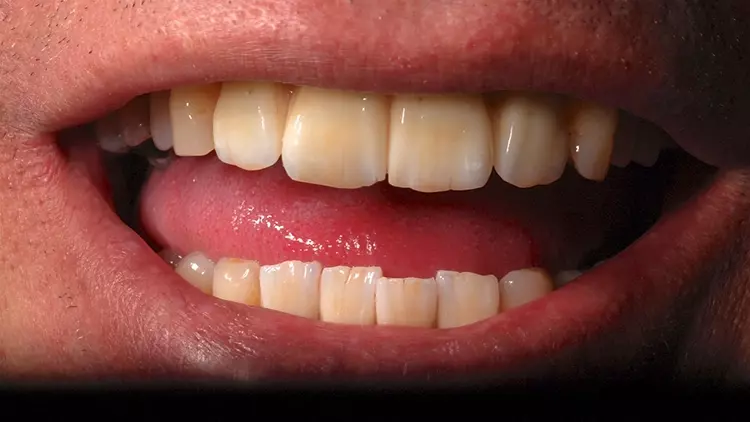

Die Restaurationen fügten sich sowohl klinisch als auch ästhetisch durch ihre spezielle Charakterisierung in die bestehende Patientensituation ein (Abb. 13-15). Auch röntgenologisch konnte eine gute Passform ermittelt werden (Abb. 16).

Der vorliegende Patientenfall beschreibt die Implantatversorgung im Ober- und Unterkiefer-Frontzahnbereich eines älteren Patienten mit einer chronischen Parodontitis und ohne systemische Erkrankungen bzw. ohne eine regelmäßige Einnahme von Medikamenten. Infolge des Attachmentverlusts konnte trotz einer Ridge Preservation mittels Sofortimplantation und einer bukkalen Auflagerung von xenogenem Knochenersatzmaterial insbesondere im Bereich der Interdentalpapillen des Oberkiefers kein ausreichender Weichgewebserhalt in vertikaler Richtung erzielt werden, was auf den Attachmentverlust infolge der Parodontitis zurückgeführt werden kann. Daher war es notwendig, die fehlenden Papillen mittels rosa eingefärbten Zirkonoxids in die Restauration zu integrieren (Abb. 13 und 14).

Der Patient wurde entsprechend instruiert, diese Bereiche täglich mittels Interdentalbürsten zu reinigen. Rezessionen wurden nicht beobachtet, was auf den dicken Phänotyp des Patienten zurückgeführt werden könnte [5]. Trotz der geringen Einschränkungen im Bereich der rot-weißen Ästhetik war der Patient mit dem ästhetischen Gesamtergebnis zufrieden.